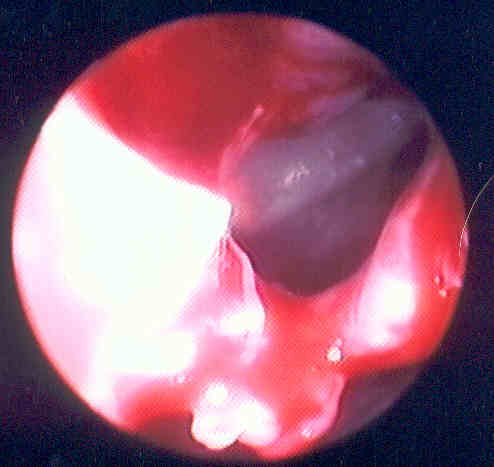

This picture displays the natural sphenoid ostia looking from the posterior ethmoid cavity, out into the spenoethmoidal recess.